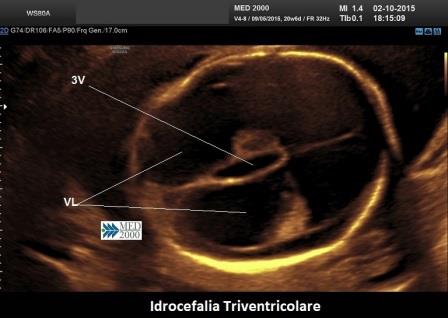

- idrocefalia triventricolare per ostruzione dell'acquedotto di Silvio

La forma di idrocefalia non comunicante più frequente è l'idrocefalia triventricolare legata all'ostruzione dell'acquedotto di Silvio (comunicazione tra III e IV ventricolo) che per il suo calibro ristretto rappresenta un punto critico dell'intera circolazione liquorale.